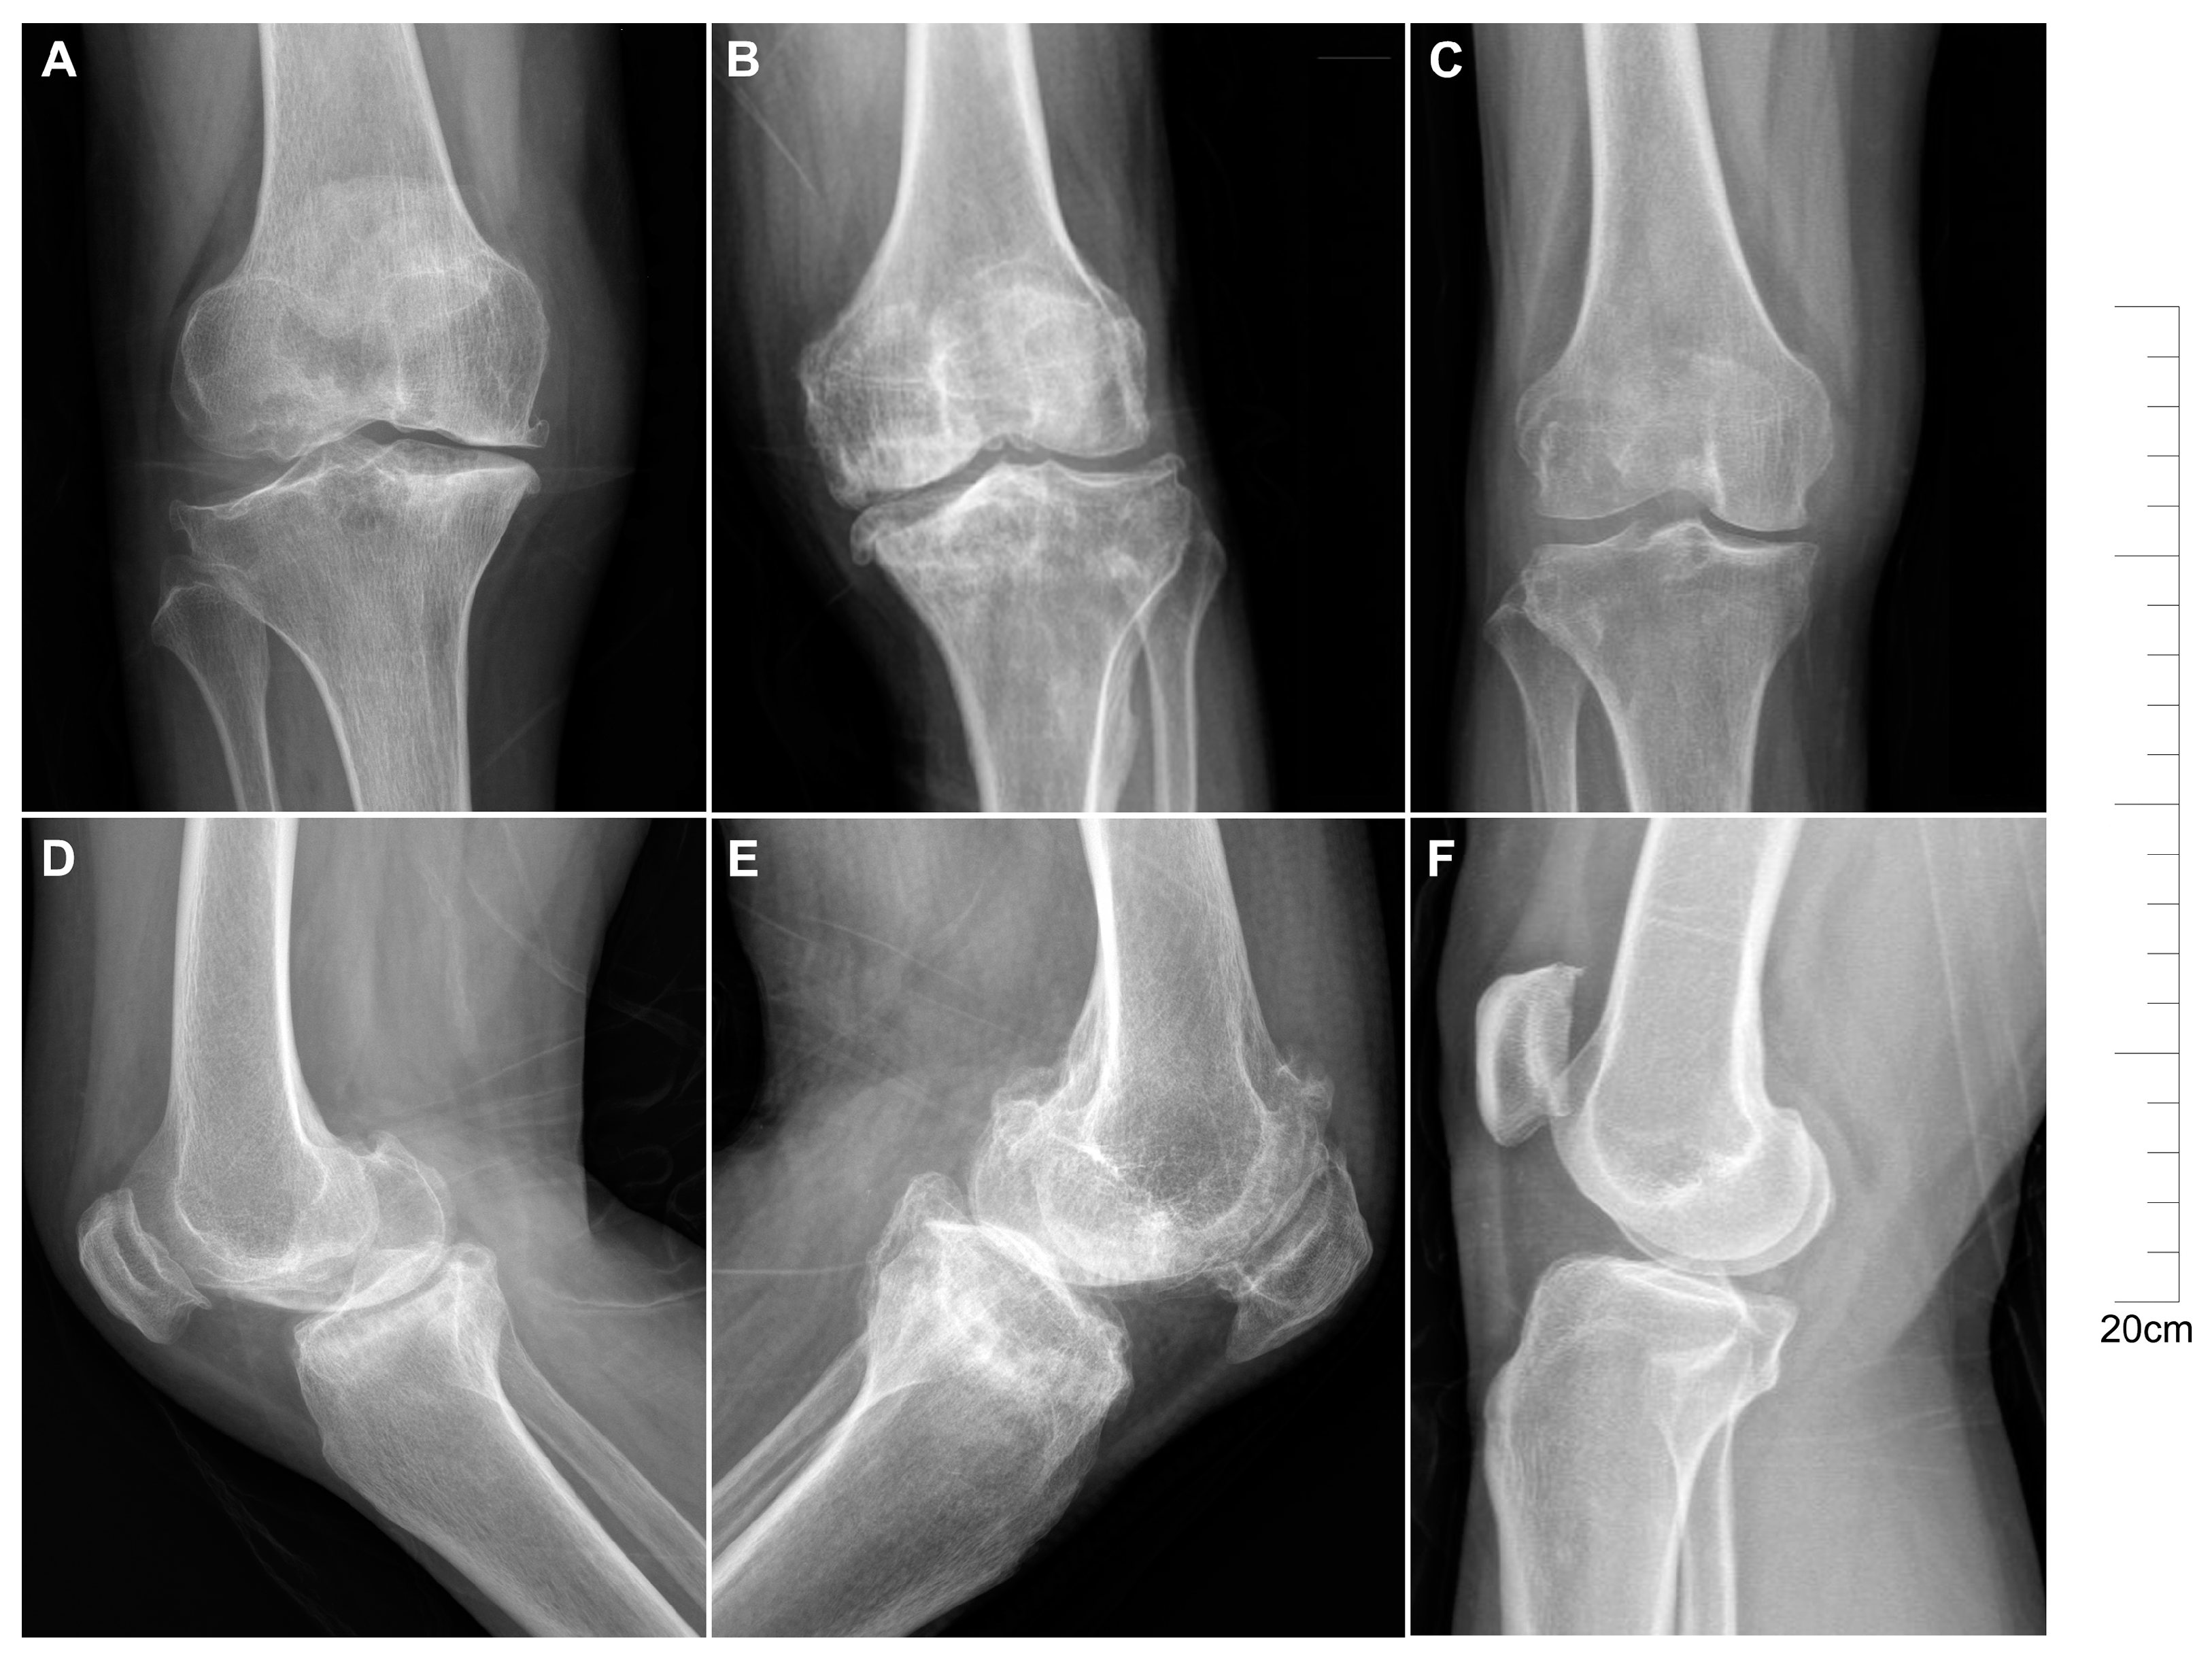

2.1. Descriptive Characteristics of Patients with KBD and OA

4.2. Patients and Samples